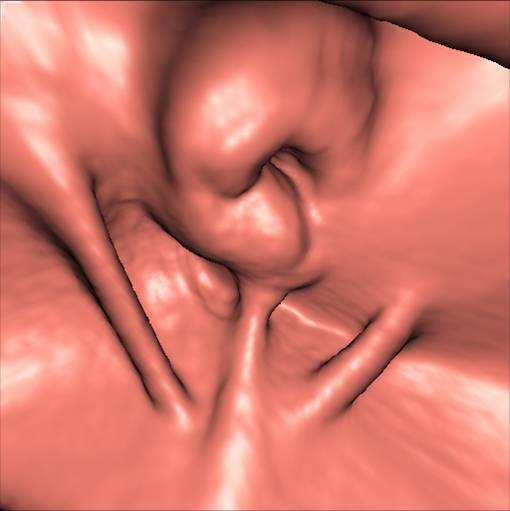

Virtuel koloskopi der viser tumoren i colon ascendens (rekonstruktion af CT-skanningen). Samme patient som illustrationen ovenfor og nedenfor.